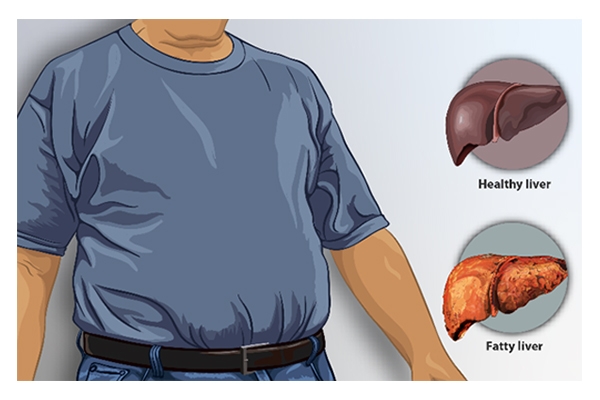

Given our lifestyle, there are many factors that lead to MASLD. According to recent studies from the Indian subcontinent, the prevalence of Metabolic dysfunction-Associated Steatotic Liver Disease in India is seen among 9–32% in the general population. As per the studies undertaken, it has been established that hypertension, type II diabetes, smoking, obesity, and dyslipidaemia are significantly associated with MASLD.

Given our lifestyle, there are many factors that lead to MASLD. According to recent studies from the Indian subcontinent, the prevalence of Metabolic dysfunction-Associated Steatotic Liver Disease in India is seen among 9–32% in the general population. As per the studies undertaken, it has been established that hypertension, type II diabetes, smoking, obesity, and dyslipidaemia are significantly associated with MASLD.